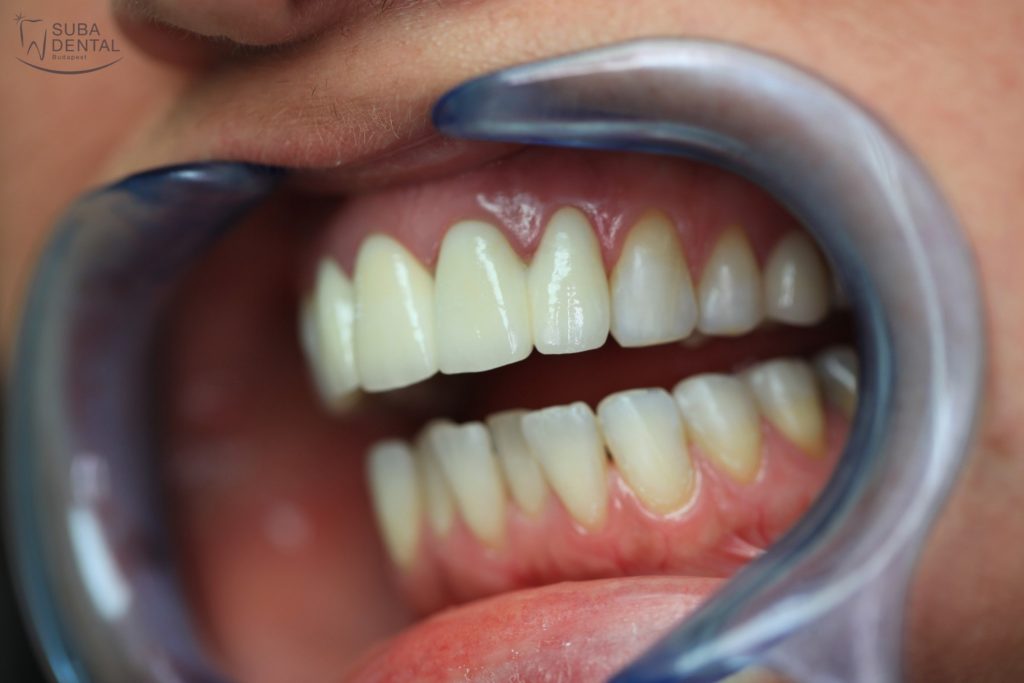

If no adjustments are required following the trial fitting of the matte teeth, the crowns are given their final glossy finish. With the permanent crowns cemented on our patient recovered his self-confidence and feels at ease to smile again.

Before

After